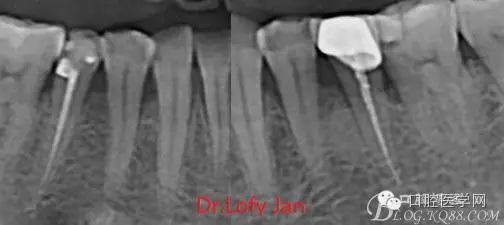

前言:自己做的一些曲面斷層片在未試尖根管治療中的病例整理,發(fā)現(xiàn)問題很多包括自身的,技術(shù)的,還有設(shè)備的問題,予以總結(jié)整理并期待進(jìn)一步提高。

根管治療術(shù)是牙體牙髓疾病治療中最復(fù)雜和最關(guān)鍵的治療項目。根管充填材料抵達(dá)根尖、并能嚴(yán)密堵塞根尖孔,是確保根管治療效果的關(guān)鍵指標(biāo)。為了保證根管充填到位,醫(yī)生需要在術(shù)前照牙片以了解牙根根管的數(shù)量、彎曲程度和長度,在術(shù)中有時需要插針照牙片來精確測量根管長度,術(shù)后必須照牙片以確定是否根管充填到位,如果欠填或超填,就需要重新充填、重新照牙片確認(rèn),直到根管充填到位。所以,在患者接受根管治療時有時會反復(fù)照牙片。

《數(shù)字化根尖片、曲面斷層片、CBCT測量牙齒長度準(zhǔn)確性的比較研究》文中顯示:平行投照數(shù)字化根尖片影像長度和牙齒實際長度之間無顯著性差異(P0.05);數(shù)字化曲面斷層片影像長度和牙齒實際長度之間有顯著性差異(P0.05),平均失真率為17.05%。CBCT冠狀面測量結(jié)果中除上頜前磨牙區(qū)、下頜前磨牙區(qū)與真實長度差異無統(tǒng)計學(xué)意義(P0.05)外,其余6個分區(qū)差異均有統(tǒng)計學(xué)意義(P0.05);矢狀面測量結(jié)果中上頜磨牙區(qū)、下頜磨牙區(qū)、下頜前磨牙區(qū)、下頜尖牙區(qū)、下頜前牙區(qū)與真實長度比較差異均有統(tǒng)計學(xué)意義(P0.05)。結(jié)論平行投照數(shù)字化根尖片較曲面斷層片和CBCT能更加精確地反映牙齒的真實長度。

病例分析:曲面斷層片在x線輔助診斷與檢查中目前大多數(shù)文獻(xiàn)和著作都建議只能作為初診拍片檢查手段,不能作為終末疾病的確診與手術(shù)療效的評價指標(biāo),臨床大部分中小型門診都因為設(shè)備不齊全導(dǎo)致信息偏差很大。